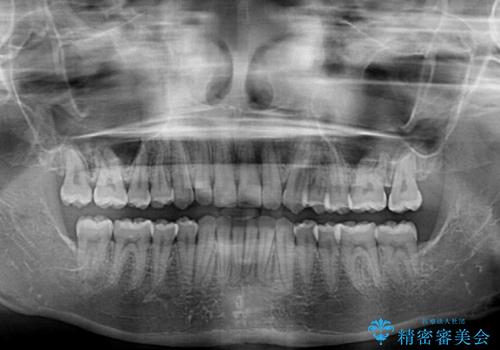

左上の歯列は補助装置により速やかに移動し、1年程度で奥歯の咬み合わせが改善され、1年3ヶ月の短期間でしっかりと仕上げることができました。